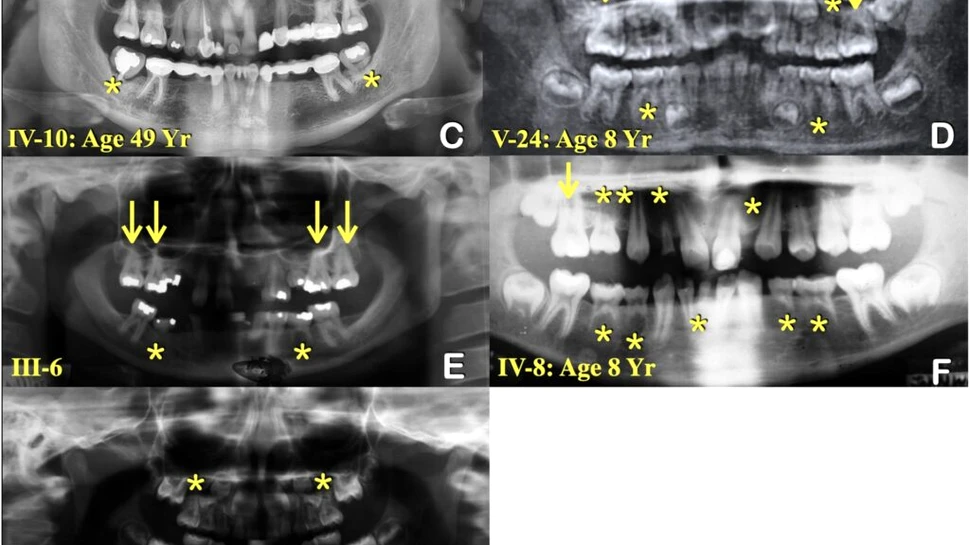

Foto: Graham Jr. et al., International Dental Journal, 2025

Pentru a găsi cauza genetică, echipa a secvențiat genomul a patru membri ai familiei, doi afectați și doi sănătoși, și a comparat rezultatele pentru a găsi mutații prezente doar la cei cu dinți lipsă. O singură mutație îndeplinea criteriile, iar aceasta se afla exact în regiunea cromozomului 1 pe care Graham o investigase cu ani în urmă.

Mutația modifica o singură „literă” din gena care produce proteina KDF-1 (keratinocyte differentiation factor 1). Această proteină controlează dezvoltarea pielii și a dinților. Pentru confirmare, cercetătorii au analizat gena la 21 de membri ai familiei: varianta modificată a apărut la 11 persoane afectate și a lipsit la cele 10 sănătoase.